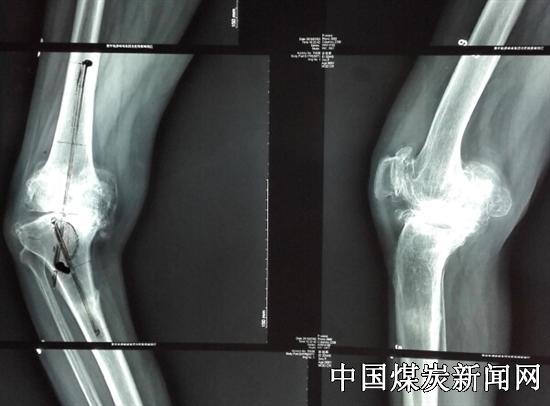

7月10日,冀中能源峰峰集团总医院邯郸骨科医院骨三科主任、共产党员韩守江立足“创”字开展科技攻关,首次成功在邯郸市利用3D打印技术开展膝关节置换术。

7月3日,就诊总医院邯郸院区的一名徐姓患者,右侧膝关节重度内翻畸形达43°,双膝关节疼痛10余年,伴脑出血后遗症,右下肢肌力减弱,左膝中度内翻畸形约20°患者行走困难,这使患者带背负极大心理压力,给她的日常生活带来极大不便。

该院骨三科主任医师韩守江从事关节置换手术近20年,手术2000多例,面对慕名而来的患者,他仔细询问病史,查看病情见患者右膝内翻严重达43°,右膝内侧胫骨平台缺损达4cm,病例极为罕见。通过研究病例,为患者制定出膝关节置换手术方案。为了准确手术,他们术前针对患者右膝详细制定截骨矫形方案,防止术中因截骨误差,导致下肢力线恢复不良,肌力弱易导致关节松弛。以为患者负责的态度,党员韩守江反复论证后,决定使用3D技术重建患者右膝关节骨性结构,通过“私人订制”定制符合个体的手术器械,施行个体化手术方案。

高科技3D打印关节技术的使用,可提前将患膝关节以实体模型方式展现出来,一方面可使主刀医生在患者身体未实施手术前,于体外进行模拟手术操作,反复、详细模拟操作,明确了术中截骨量大小及力线纠正方案;另一方面,通过3D模型同时为患者定制专用个体手术器械——“截骨模板”,极大的改善通用器械对复杂病例的处理局限,提高手术精度和成功率。简言之,可达到,“未开刀,已手术”的超前效果。3D打印技术为工业发展带来革命,同样3D打印关节置换技术,将人工关节置换可“私人订制”。藉此,韩守江主任同时对患者徐某行双膝关节置换手术,手术完成后,患者下肢力线满意,目前恢复良好,患者已下地行走。